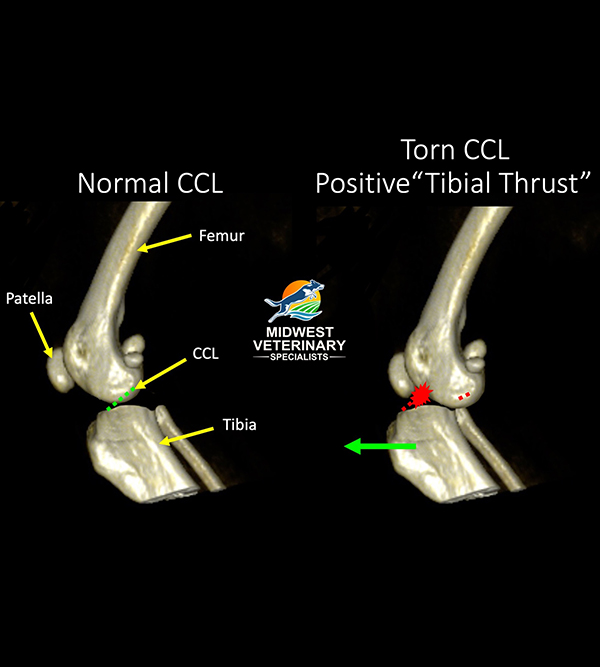

Your dog’s stifles (i.e., knee joints) absorb a lot of impact as they run, jump, and play. To understand cranial cruciate ligament rupture, you must first understand the components of the stifle joint. This stifle is composed of the femur (i.e., thigh bone), tibia (i.e., shin bone), and patella (i.e., kneecap). Four ligaments—the cranial cruciate, caudal cruciate, medial collateral, and lateral collateral ligaments—are primarily responsible for stabilizing the stifle. The medial and lateral menisci act as cushions between the femur and tibia, and help provide congruency and further stabilize the joint.

The canine cranial cruciate ligament (CCL), which is the anatomical equivalent to the human anterior cruciate ligament (ACL), has three functions:

- It limits hyperextension of the stifle

- It limits internal rotation of the tibia, relative to the femur

- It prevents front-to-back sliding motion (i.e., drawer motion) of the tibia relative to the femur.